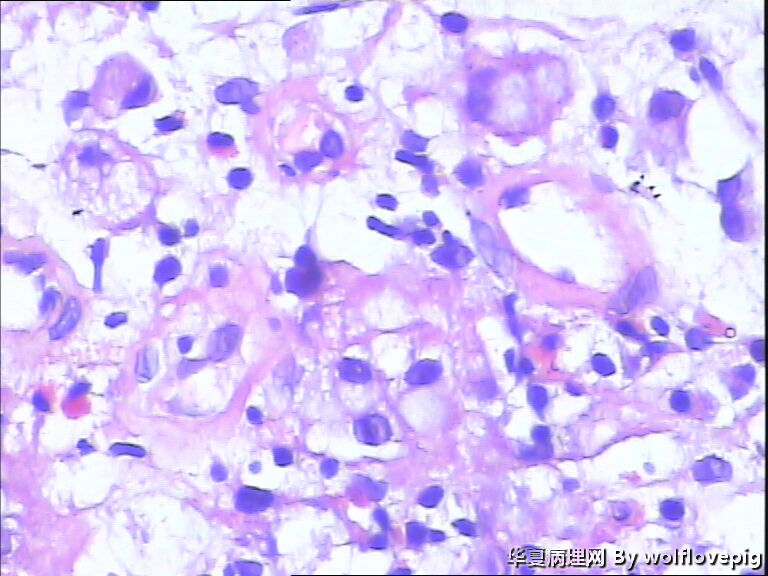

男,60y,胃窦呈结节样改变。

• 请教!胃镜活检。图2

图2

印戒细胞癌

胃印戒细胞癌

低分化腺癌(含印戒细胞癌)

粘液腺癌,部分呈印戒细胞癌。

黏液腺癌。

肿瘤中含有50%的细胞外黏液池,黏液中漂浮着散在或串珠状的癌细胞,癌细胞为富含黏液的柱状细胞及印戒细胞。

粘液腺癌,倾向于印戒细胞癌

粘液腺癌

黏液腺癌为主,部分呈印戒细胞癌